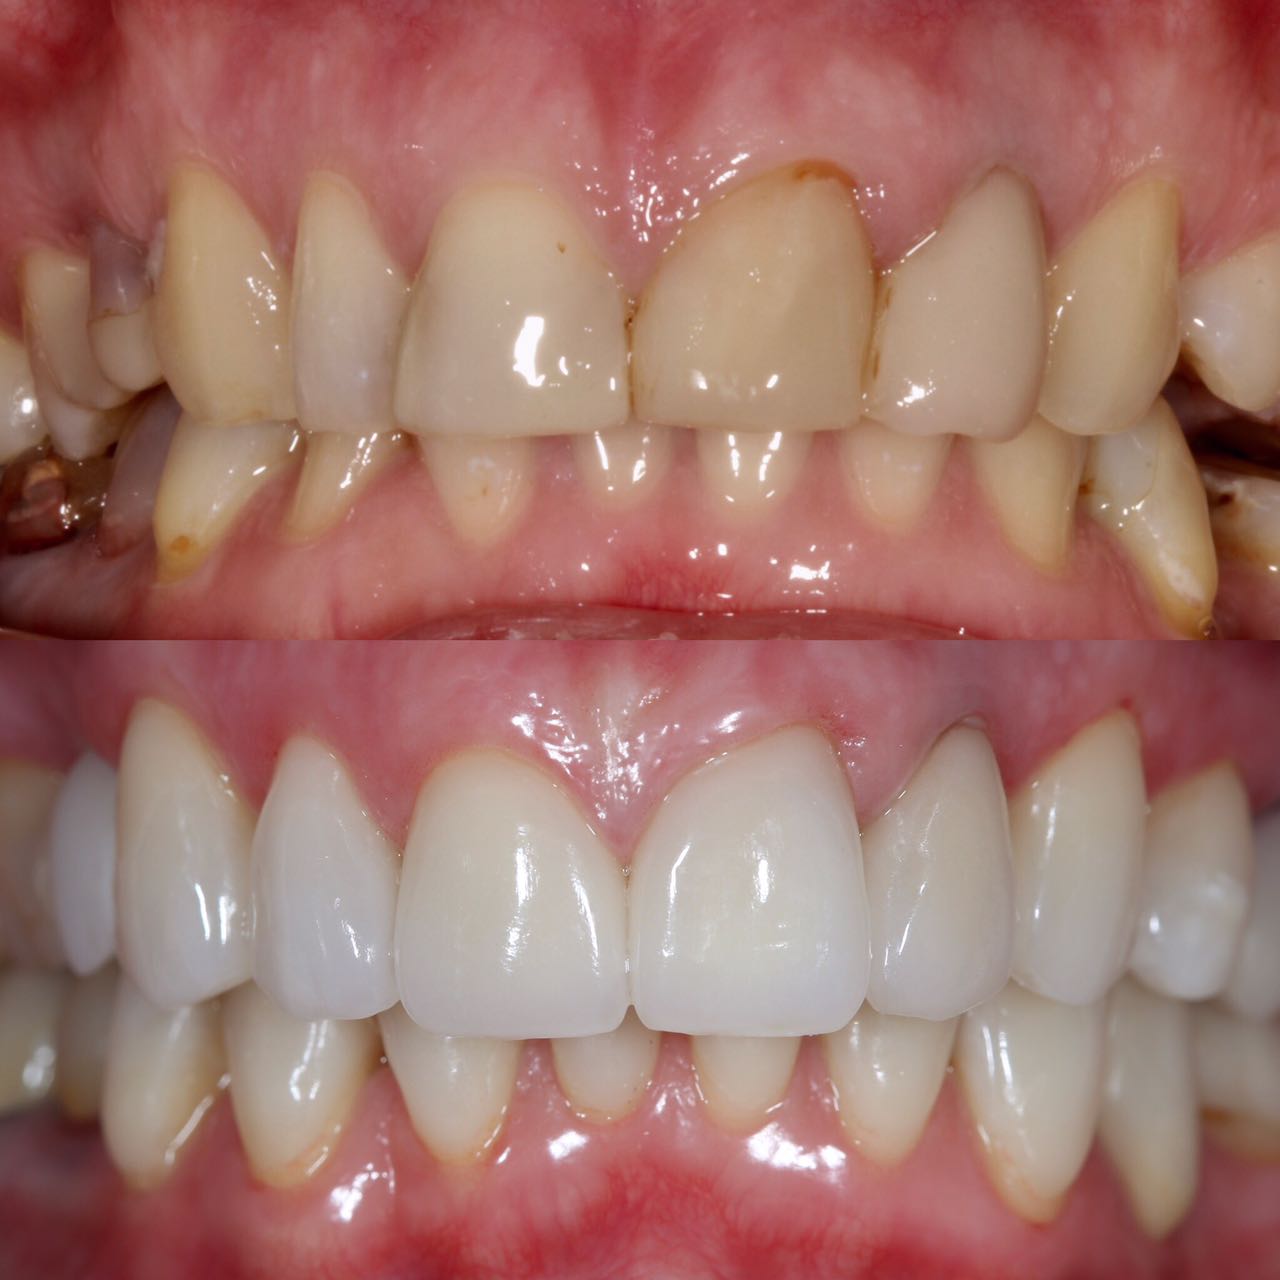

Белые виниры BLEACH

Все чаще стали поступать заказы на виниры цвета BLEACH. Очень красивый результат. Улыбка становится очень красивой.

Это виниры на рефракторе . 12 зуб коронка на оксиде циркония.